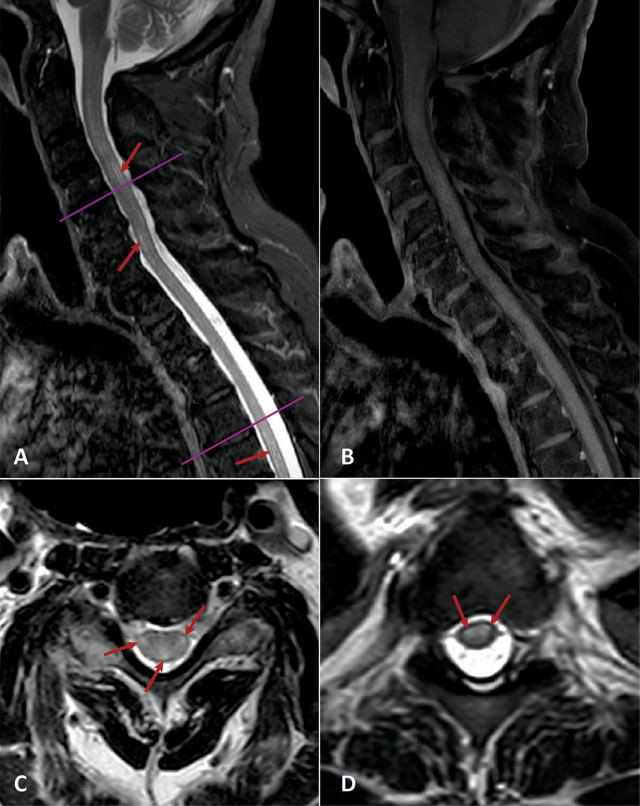

Вік пацієнтів, що вивчаються, варіювався від 21 до 73 років, і це захворювання зачіпало чоловіків і жінок приблизно з однаковою частотою. У всіх пацієнтів, розглянутих у дослідженні, був параліч і втрата чутливості, а медична візуалізація показувала наявність уражень спинного мозку.

Вік пацієнтів, що вивчаються, варіювався від 21 до 73 років, і це захворювання зачіпало чоловіків і жінок приблизно з однаковою частотою. У всіх пацієнтів, розглянутих у дослідженні, був параліч і втрата чутливості, а медична візуалізація показувала наявність уражень спинного мозку.